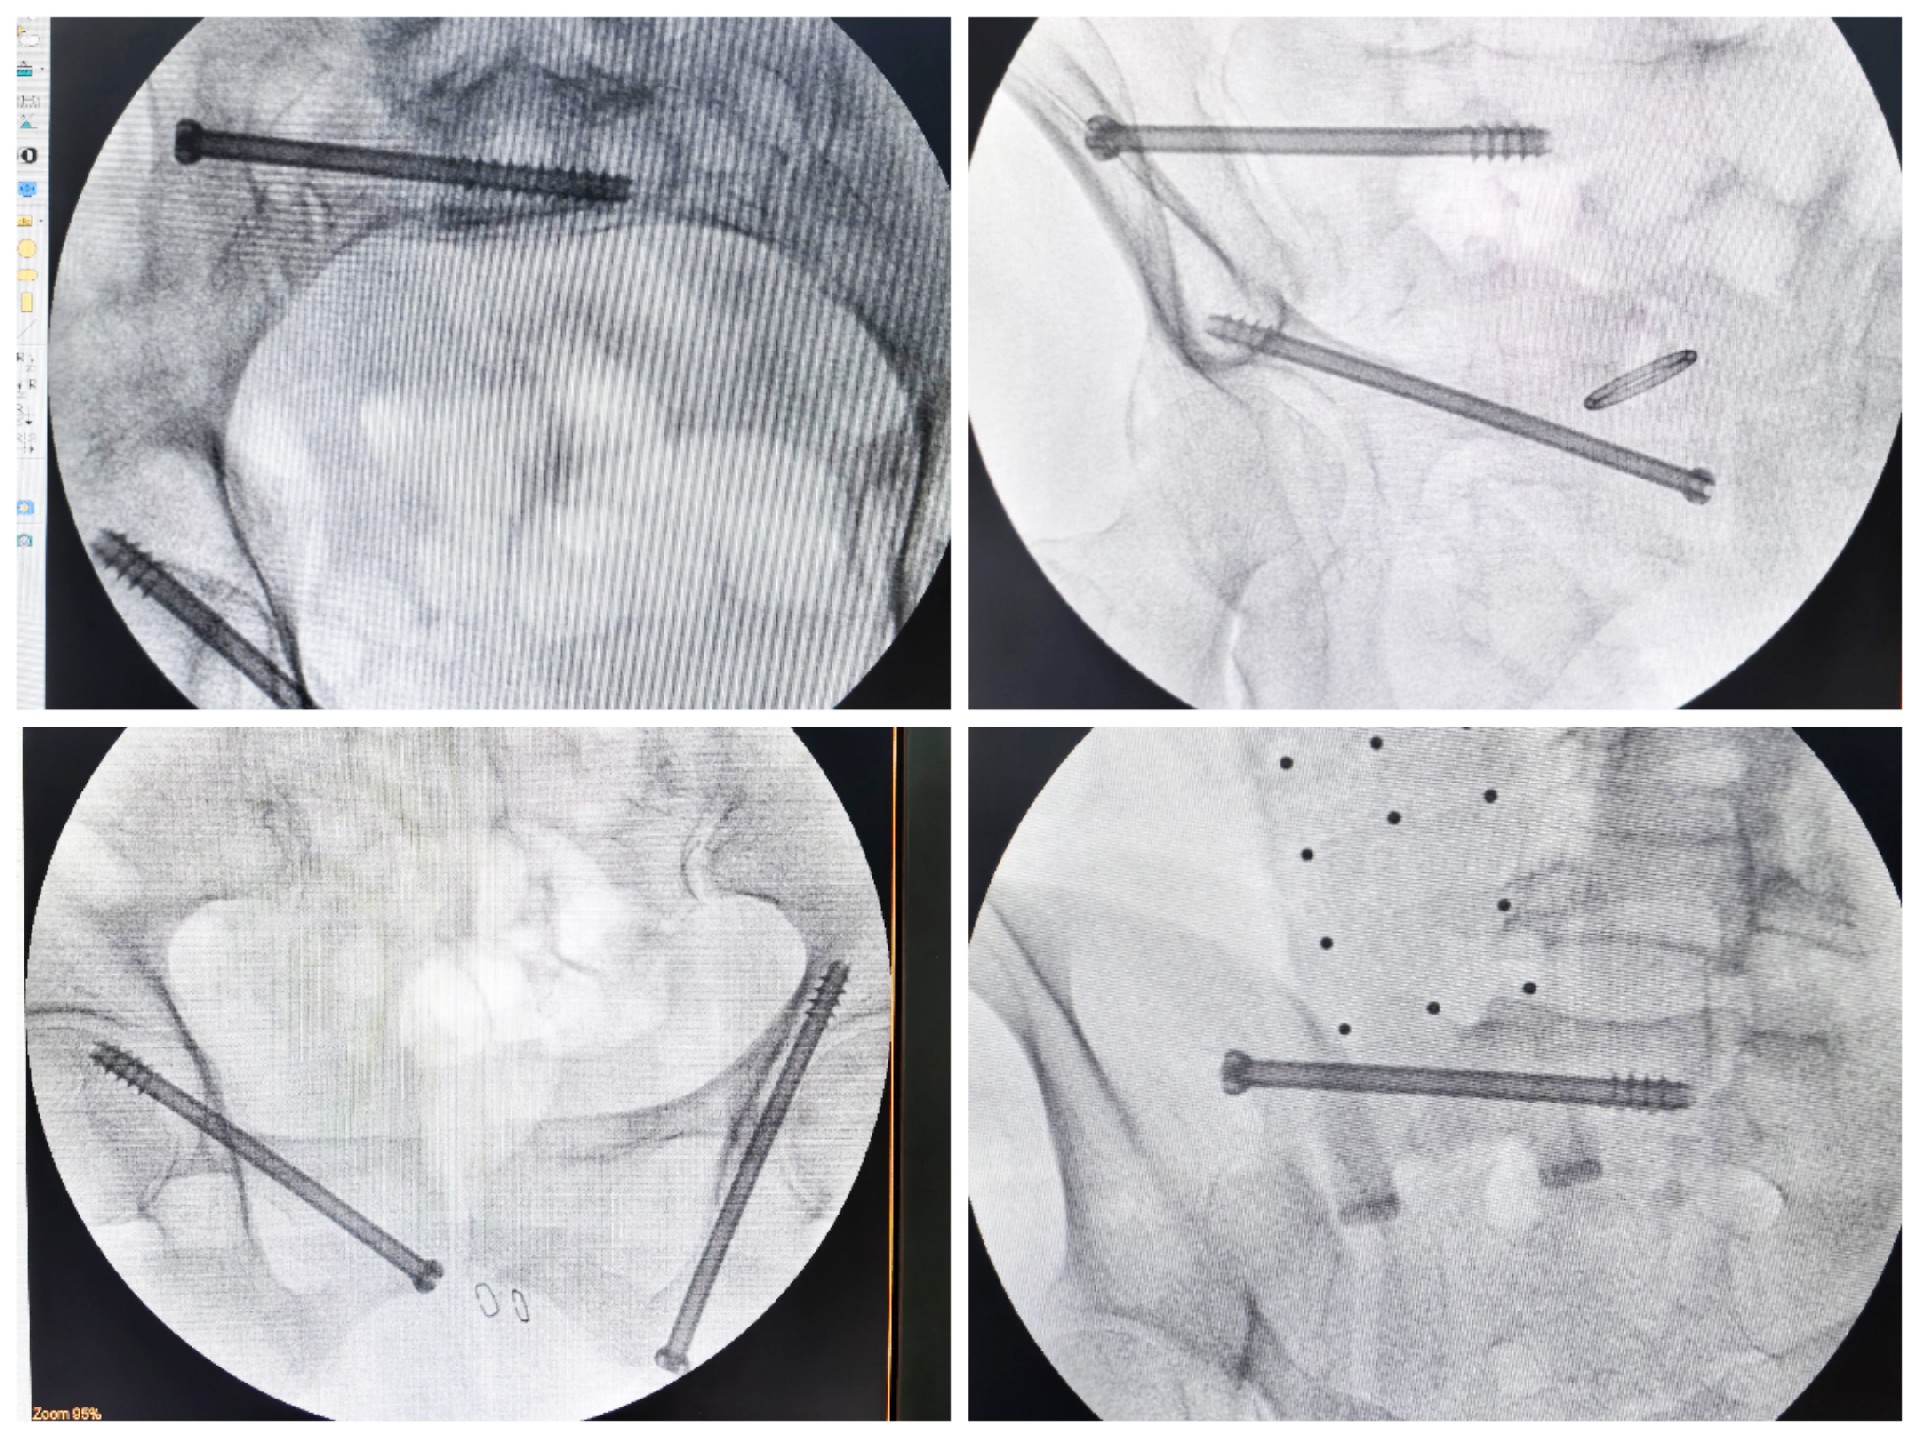

傳統(tǒng)的骨盆骨折微創(chuàng)手術(shù)中,骶髂螺釘?shù)嚷葆斨萌氲碾y點(diǎn)在于骨盆部位解剖十分復(fù)雜,螺釘置入如有偏差極易損傷重要神經(jīng)及血管,手術(shù)不僅依靠手術(shù)醫(yī)師豐富的經(jīng)驗(yàn),還需要術(shù)中反復(fù)的C型臂透視及調(diào)整,對(duì)患者及醫(yī)生都有較大輻射。而利用HoloSight知見創(chuàng)傷骨科機(jī)器人進(jìn)行骨盆骨折微創(chuàng)手術(shù),通過高精度光學(xué)定位追蹤技術(shù)與混合現(xiàn)實(shí)技術(shù),使整個(gè)微創(chuàng)手術(shù)全程可視化,可以在電腦屏幕上實(shí)時(shí)顯示螺釘?shù)木珳?zhǔn)置入位置,降低手術(shù)風(fēng)險(xiǎn),提高手術(shù)效率及安全性。

術(shù)前,手術(shù)團(tuán)隊(duì)認(rèn)真分析討論病例,全面掌握骨盆骨折微創(chuàng)治療的關(guān)鍵技術(shù),提前設(shè)計(jì)手術(shù)方案并反復(fù)模擬演練手術(shù)過程。術(shù)中,利用HoloSight知見創(chuàng)傷骨科機(jī)器人規(guī)劃骨折復(fù)位方案及定位螺釘通道,實(shí)現(xiàn)精準(zhǔn)微創(chuàng)手術(shù)。手術(shù)通過不足1cm小切口完成,最大程度地減少了術(shù)中出血,術(shù)中幾乎都是一次性成功精準(zhǔn)微創(chuàng)地置入內(nèi)固定螺釘,減少了醫(yī)源性操作對(duì)骨折周圍骨質(zhì)的影響,實(shí)現(xiàn)骨折微創(chuàng)固定的同時(shí)盡可能提高骨折固定的穩(wěn)定性,為術(shù)后患者的快速康復(fù)創(chuàng)造了有利條件。